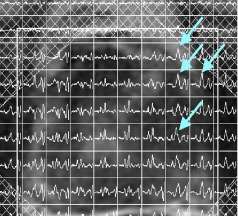

LEFT: T2-weighted imaging: hypointense focus left anterior apex (horizontal arrow) with uninvolved neurovascular bundle (vertical arrow)

CENTER: Colorized apparent diffusion coefficient (ADC) map: moderately restricted diffusion (yellow arrow)

RIGHT: Colorized dynamic contrast enhanced (DCE) perfusion map: focal intense enhancement